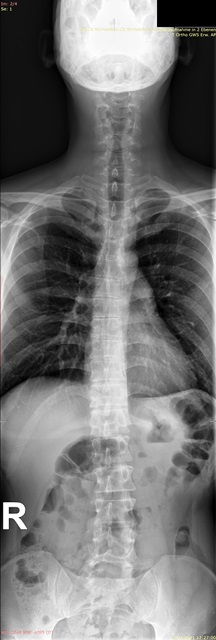

Habe die Bilder. Für mich als Laie sieht es nicht so schlimm aus auf den Röntgenaufnahmen, aber ich bin in der Realität total asymmetrisch und schief, und am extremsten ist, dass die Rippen/Brustkorb auf der rechten Seite viel mehr rausstehen und das optisch sehr auffällt.

Ich (auch Laie) sehe nur eine geringe Seitabweichung der Wirbelsäule, aber eine deutliche Rotation, erkennbar an den "Kringeln" der Dornfortsätze und Querfortsätze. Ich denke auch, dass da ein Spezialist gefragt ist.rudi777 hat geschrieben: ↑Do, 22.04.2021 - 16:20 Für mich als Laie sieht es nicht so schlimm aus auf den Röntgenaufnahmen, aber ich bin in der Realität total asymmetrisch und schief, und am extremsten ist, dass die Rippen/Brustkorb auf der rechten Seite viel mehr rausstehen und das optisch sehr auffällt.

Die Rotation ist das Problem, denke ich auch. Kann man da was machen? Ist das eine Sache für einen Orthopäden oder was meinst du mit Spezialist? Danke.Lady S hat geschrieben: ↑Do, 22.04.2021 - 19:45Ich (auch Laie) sehe nur eine geringe Seitabweichung der Wirbelsäule, aber eine deutliche Rotation, erkennbar an den "Kringeln" der Dornfortsätze und Querfortsätze. Ich denke auch, dass da ein Spezialist gefragt ist.rudi777 hat geschrieben: ↑Do, 22.04.2021 - 16:20 Für mich als Laie sieht es nicht so schlimm aus auf den Röntgenaufnahmen, aber ich bin in der Realität total asymmetrisch und schief, und am extremsten ist, dass die Rippen/Brustkorb auf der rechten Seite viel mehr rausstehen und das optisch sehr auffällt.

Wie ich gerade geschrieben habe, finde ich, dass man die Rotation sieht - kannst Du das nachvollziehen?